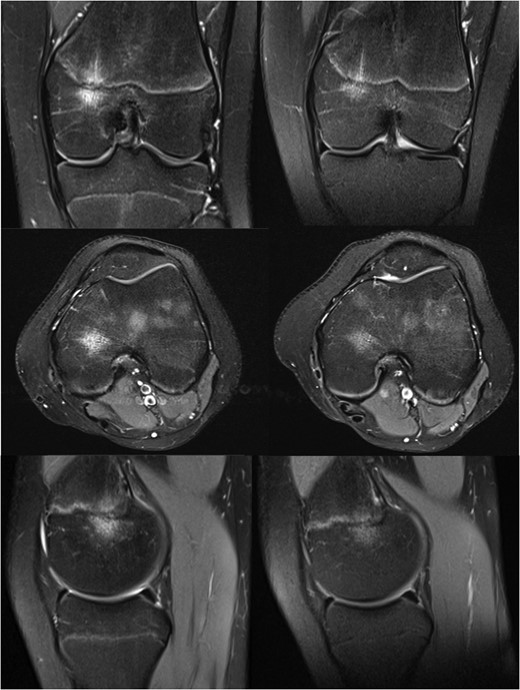

MRI images of the knee at 9 (left) and 13 months (right) after initial injury.

Her symptoms gradually improved without treatment, and with the significant improvement seen on her MRI scan she was eventually discharged from our care fourteen months after her initial injury.

On examination at nine months she had medial tenderness and a positive McMurray's test, raising the suspicion of meniscal injury, for which the initial MRI investigation was performed. This scan showed a focal region of oedema centred in the medial aspect of the distal femoral physis with no other internal derangement, and she was managed with observation.